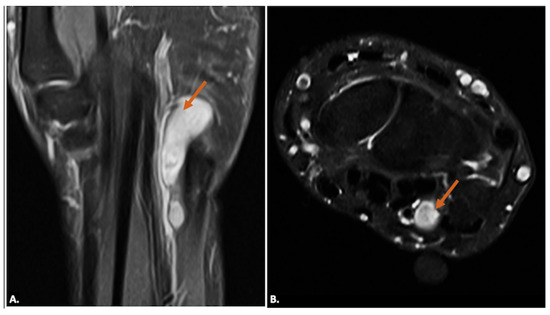

Other pathological conditions affecting Guyon’s canal include vascular abnormalities such as arteriovenous malformation (Figure 15), ulnar artery thrombosis, tortuosity (Figure 16), or aneurysms. Ultrasound imaging will show hypoechoic or anechoic mass with vascular flow seen on Doppler imaging in cases of aneurysm with absence of flow in a case of thrombosis. On MRI, thrombosis is seen as low or high signal intensity within the vessel lumen on both T1- and T2-weighted images, depending on duration. Aneurysms appear as well-circumscribed lesions, potentially with signal voids due to high flow. Pseudoaneurysm will show the presence of adjacent soft-tissue mass in close approximation with the lumen [23].

Figure 15.

(A) T1-weighted axial, (B) T2-weighted, fat-suppressed axial, and (C) T2-weighted, fat-suppressed coronal MR images of an arteriovenous malformation (indicated by the orange arrow) in the region of Guyon’s canal. The lesion appears hypointense on the T1-weighted sequence (A), appears hyperintense on T2-weighted, fat-suppressed sequences, (B) and demonstrates continuity with vessels (blue arrows) (C).

Figure 16.

(A) T2-weighted, fat-suppressed coronal and (B) T2-weighted, fat-suppressed axial MR images reveal the tortuous irregular path of the ulnar artery (orange arrow) in the region of Guyon’s canal, resulting in ulnar neuropathy and causing neuropathic symptoms.